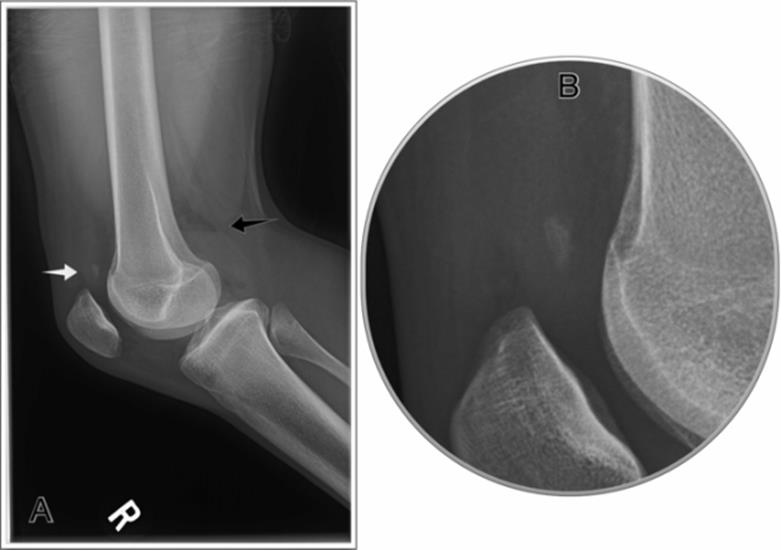

· Plain radiographs – diagnostic if the joint is still subluxed/dislocated (Figure 4.5 A, B)

· May be normal if reduced already

· May see associated fractures of the femur or tibia, (including avulsion fractures)

Figure 4.5 Lateral knee dislocation compared to an anterior/posterior knee dislocation, a lateral dislocation is more likely to have a common peroneal nerve palsy, and less likely to have an arterial injury, though both complications can occur with any knee dislocation. A: AP view. B: Lateral view. (Images courtesy of Arun Sayal, MD.)